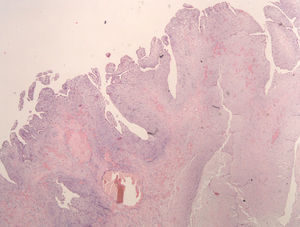

Dados anatómicosO MC localizava-se na aurícula esquerda em 92,5% dos casos (37 doentes), na aurícula direita em 2 doentes (5%) e no ventrículo esquerdo (com inserção no músculo papilar posterior da válvula mitral) em um doente (2,5%). A inserção ocorria na fossa ovalis do SIA (face auricular esquerda) em 53% dos casos (mas apenas 57% dos casos de MC da aurícula esquerda apresentavam esta inserção dita típica) e registava-se fora do SIA em 30% dos doentes. O pedículo do MC era curto e largo ou inexistente (MC séssil) em 16 doentes (40% dos casos). Macroscopicamente, o MC apresentava características vilosas (com substrato anatomopatológico papilar ou pseudopapilar) em 35% dos doentes (14 casos) – Figura 1; nos restantes, revelava-se como um tumor ovoide ou esférico, de superfície lisa (Figura 2). O tamanho médio do tumor era de 4,6 x 3,7 centímetros.

Os tumores são mais frequentemente revestidos por uma camada única de células achatadas, mas o revestimento pode ser estratificado e com pequenos gomos celulares. Frequentemente, há trombos aderentes à superfície tumoral. Na nossa série, uma superfície pelo menos em parte papiliforme ou vilositária (Figura 6) foi observada em 14 casos (35%).